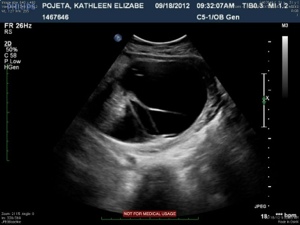

The next four images just show various views of the strands/septations that are visible within the sac.

20120921-213531.jpg